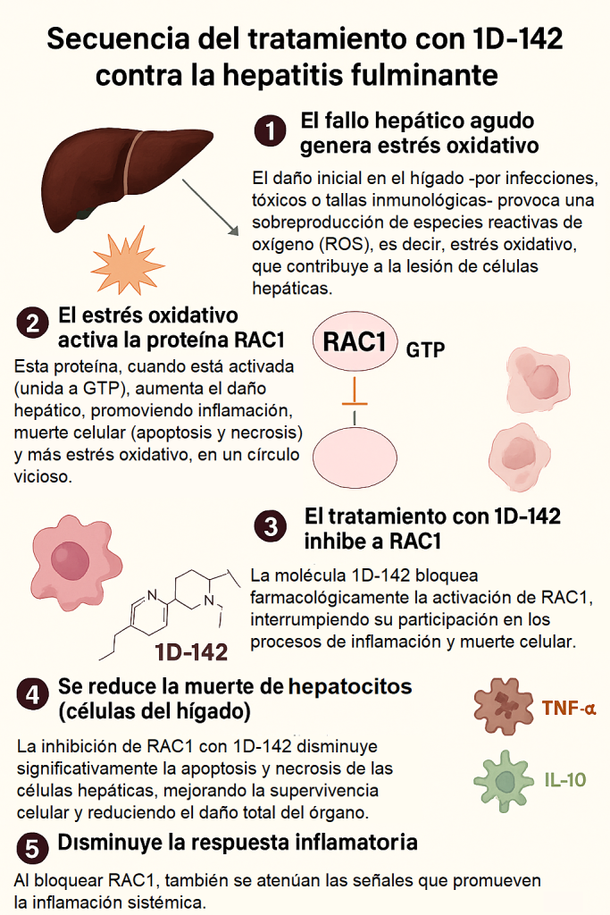

Investigadores de la Universidad Austral y el CONICET validaron una nueva terapia para reducir el daño hepático.

También se observó menor acumulación de radicales libres (ROS), menor infiltración de células inflamatorias y menor expresión de citoquinas proinflamatorias.

Como conclusión, el tratamiento redujo casi a la mitad los indicadores de daño hepático en sangre, lo que sugiere que los hígados tratados sufrieron considerablemente menos que aquellos que no recibieron la molécula.

El descubrimiento fue realizado por científicos del Laboratorio de Hepatología Experimental y Terapia Génica del del Instituto de Investigaciones en Medicina Traslacional (Universidad Austral / CONICET) y recientemente aceptado para publicación en Journal of Hepatology Reports.

El estudio, parte de la tesis doctoral de Bárbara Bueloni, fue realizado bajo la dirección de los doctores Guillermo Mazzolini y Juan Bayo, con la colaboración de Julieta Comin del INTI y el apoyo de la empresa biotecnológica Spectrum.